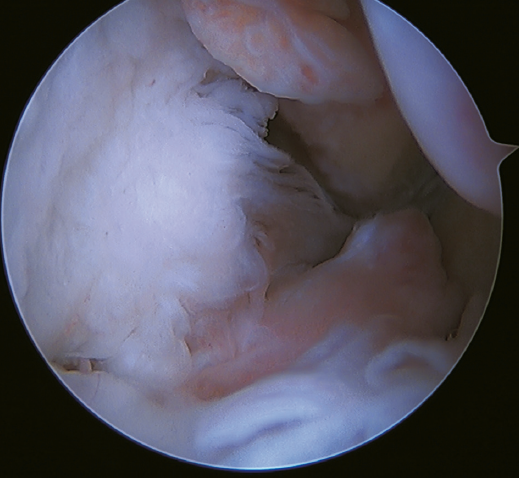

Tratamiento artroscópico de la inestabilidad rotacional/multidireccional

La inestabilidad rotacional es un concepto relativamente novedoso descrito en 2011 por Buchhorn(67), donde se describen lesiones combinadas del complejo lateral y del ligamento deltoideo, y una técnica de reconstrucción anatómica para ambas lesiones. Aunque no existe evidencia biomecánica de por qué se produce la lesión medial en pacientes que no han sufrido traumatismos en eversión, probablemente el estrés mantenido sobre el complejo medial en la inestabilidad lateral puede evolucionar a una inestabilidad rotacional, lo cual va en línea con la teoría del efecto dominó previamente explicada(5,62). Se estima que hasta el 10-15% de las ICLT pueden evolucionar a la lesión del complejo medial, afectando especialmente sus fibras más anteriores. Recientemente, Vega(68) describe la combinación de lesiones del complejo lateral con la lesión en “hoja de libro” (Figura 7) del fascículo tibiotalar superficial del ligamento deltoideo debido a la excesiva rotación interna en la inestabilidad lateral crónica, así como su tratamiento mediante reparación directa de ambas lesiones. Acevedo(34) y Vega(68) también describen la posición de seguridad de los anclajes en el maléolo medial.